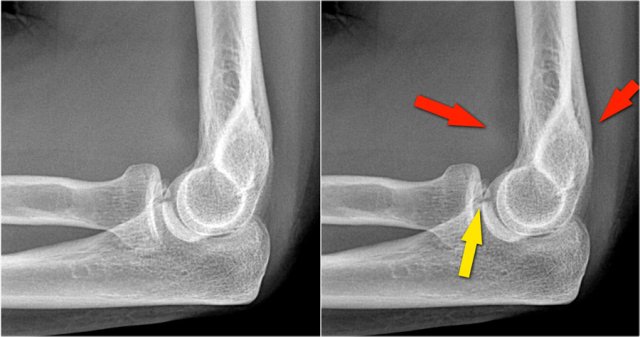

Here a lateral view of the elbow of a patient who fell on the outstretched arm.

The radiograph shows joint effusion (red arrows) and a coronoid fracture (yellow arrow).

Continue with the MR-images.

Coronal view:

1. Lateral collateral ligament is completely stripped (yellow arrow).

2. radial head is subluxed.

3. marrow edema of the coronoid process due to the fracture (red arrow).

Sagittal view:

1. Radial head is a little bit subluxed posteriorly (yellow arrow).

2. Large effusion and capsular disruption posteriorly.

3. Contusion of the posterior side of the capitellum as a result of impaction by the coronoid process (red arrow).

All these signs are the result of a posterior dislocation.